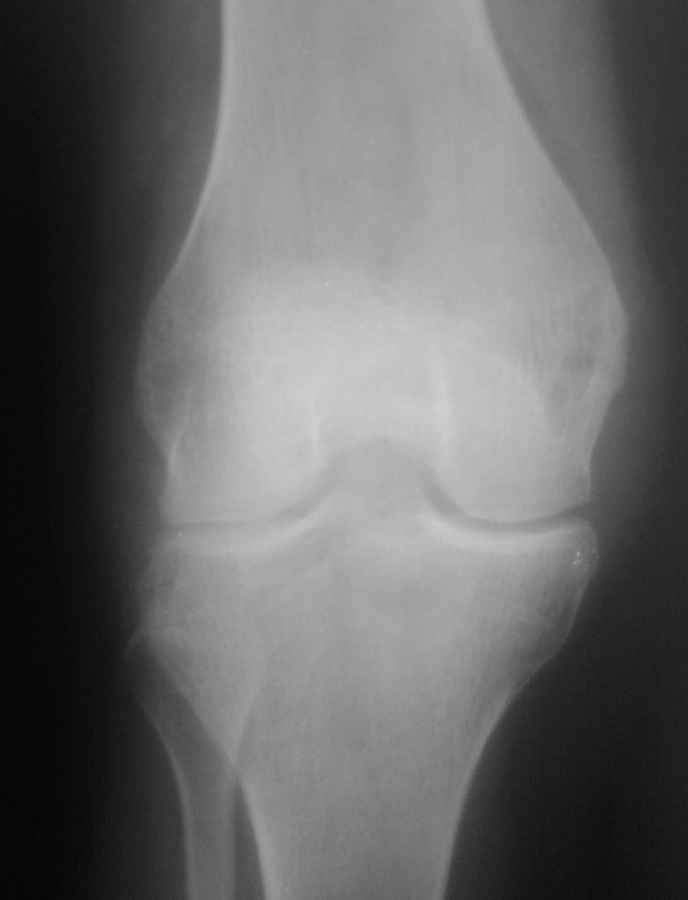

Гонартроз 2ст по Косинской. Рецидивирующие синовииты.

В настоящий момент без наличия травмы - пациентка пришла домой почувствовала боли в коленном суставе, утром коленныйц сустав дословно "разбух", за помощью не обратилась, пила НПВС. Обратилась на 4 сутки При поступлении определяется выраженный отёк, сглаженность контуров коленного сустава, симптомы баллотирования, подковы ярко выражены - кожные покровы теплее окружающих мягких тканей, осевая нагрузка резко болезненна. Пункция - 90мл синовиальной жидкости, насыщенного жёлтого цвета слегка мутновата,с хлопьями. Отправлена на цитологическое исследование. Наложена 2ух лонгетная гипсовая повязка, назначены АБ.На снимках - уменьшение просвета щели коленного сустава, краевые разрастания, видно разряжение плотности эпиметафизарной части бедренной и б\берцовой костей - кистозная перестройка? Мнения по тактике!